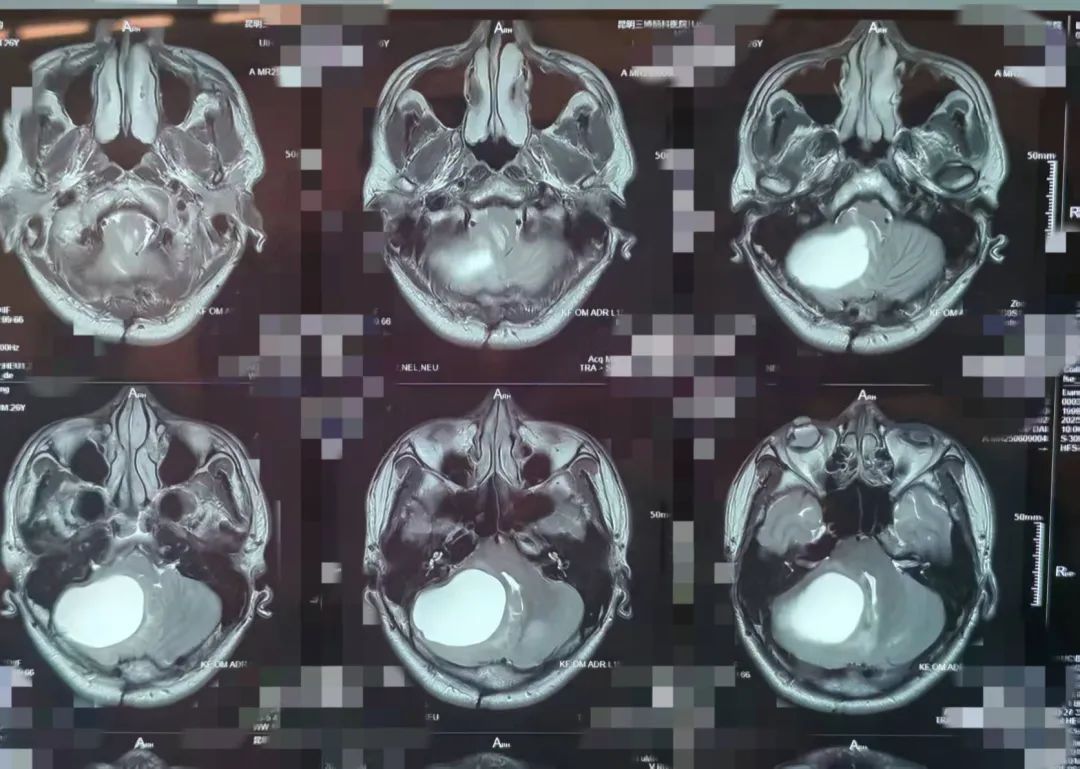

作为新院区启用后,神经外二科的「第一刀」,本次手术由神经外二科团队精心筹备,名誉院长张永力主刀,科室副主任王浩然等配合,凭借丰富的临床经验和先进的医疗设备,为一名 25 岁男性患者行「右侧枕下乙状窦后入路病变切除术」。